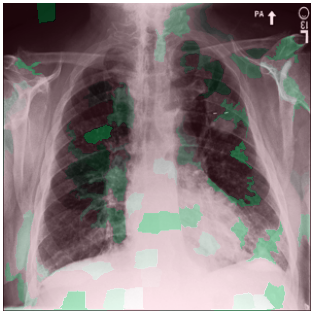

3.3 Interpretability

Post-Hoc Comparisons. We compare our concept-based explanations to post-hoc XAI techniques LIME and SHAP, applied to the baseline InceptionV3 model. The image explanations generated by these techniques disagree with each other and the medical ground truth. We show an example of this observation in Figure 7, where both techniques fail to capture the large mass in the X-ray, and highlight irrelevant regions such as areas outside of the lung as incorrectly important to the classification decision. In contrast, our approach correctly identifies the presence of a mass. More examples are shown in Figure 10.

Refer to caption

(a) Ground Truth

(b) LIME

(c) SHAP

(d) CXR-LLaVA Generated Report

(e) Our Approach

Figure 7: Example of our explanation approach outperforming LIME, SHAP and CXR-LLaVA. Ground truth (a) is a “Large right upper zone mass". LIME (b) and SHAP (c) fail to capture the mass in the X-ray. Most important image regions are bounded by yellow for LIME, and shown in more vibrant green for SHAP. CXR-LLaVA (d) generates a report which wrongly describes the image as non-cancerous. Our approach (e) correctly identifies the presence of a mass.

(a) Ground Truth 1

(b) Ground Truth 2

(c) Ground Truth 3

(d) Ground Truth 4

(e) LIME 1

(f) LIME 2

(g) LIME 3

(h) LIME 4

(i) SHAP 1

(j) SHAP 2

(k) SHAP 3

(l) SHAP 4

Figure 10: Examples of LIME and SHAP explanations failing to capture the medical ground truth of a cancerous chest X-ray, while also generating conflicting explanations. Ground truth (a,b,c,d) is shown as red squares. Most important regions are bounded by yellow for LIME (e,f,g,h) and shown as more vibrant green for SHAP (i,j,k,l).